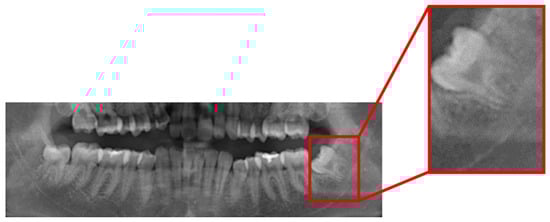

This study proposes a tooth segmentation algorithm based on vertical grayscale projection, which aims to automatically detect and segment teeth in DPR images. Vertical grayscale projection is used to analyze the brightness distribution in different regions. It is employed to identify the positions of tooth clefts, as shown in Figure 8a. Subsequently, teeth are segmented based on the characteristics of the projection distribution, as shown in Figure 8b,c. This algorithm exhibits excellent applicability and efficiency in oral image processing.

Figure 8. Vertical grayscale projection algorithm (a), vertical grayscale projection, (b) left impacted tooth, and (c) right impacted tooth.